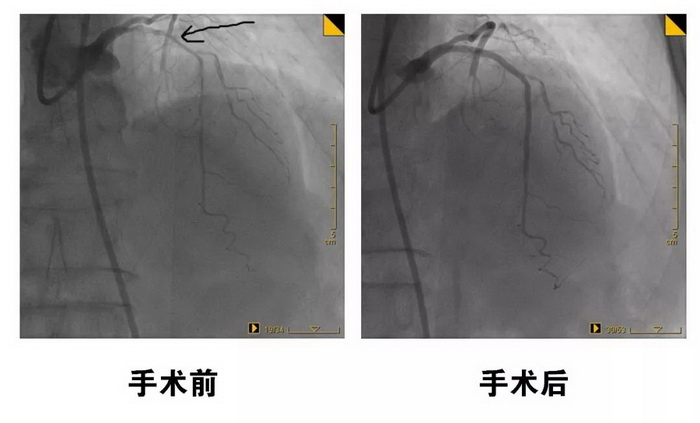

2月14日,心内科心脏介入团队首先为患者开通右冠状动脉,放置了三枚支架。随后,高希春主任组织科室人员进行讨论分析,认为患者左冠状动脉钙化严重,必须采用目前最先进的冠状动脉旋磨术,制定了详细的手术流程及并发症的处理措施。4月3日,在介入导管室的积极配合下,心内科心脏介入团队为患者实施了冠状动脉旋磨术及支架置入术,经过6次旋磨,成功在患者左前降支放了两枚支架,解除了李奶奶的心绞痛症状。 这是我县首次应用冠状动脉旋磨术处理冠脉严重钙化病变并取得圆满成功,标志着桓台县心脏介入水平又迈上了一个新台阶。